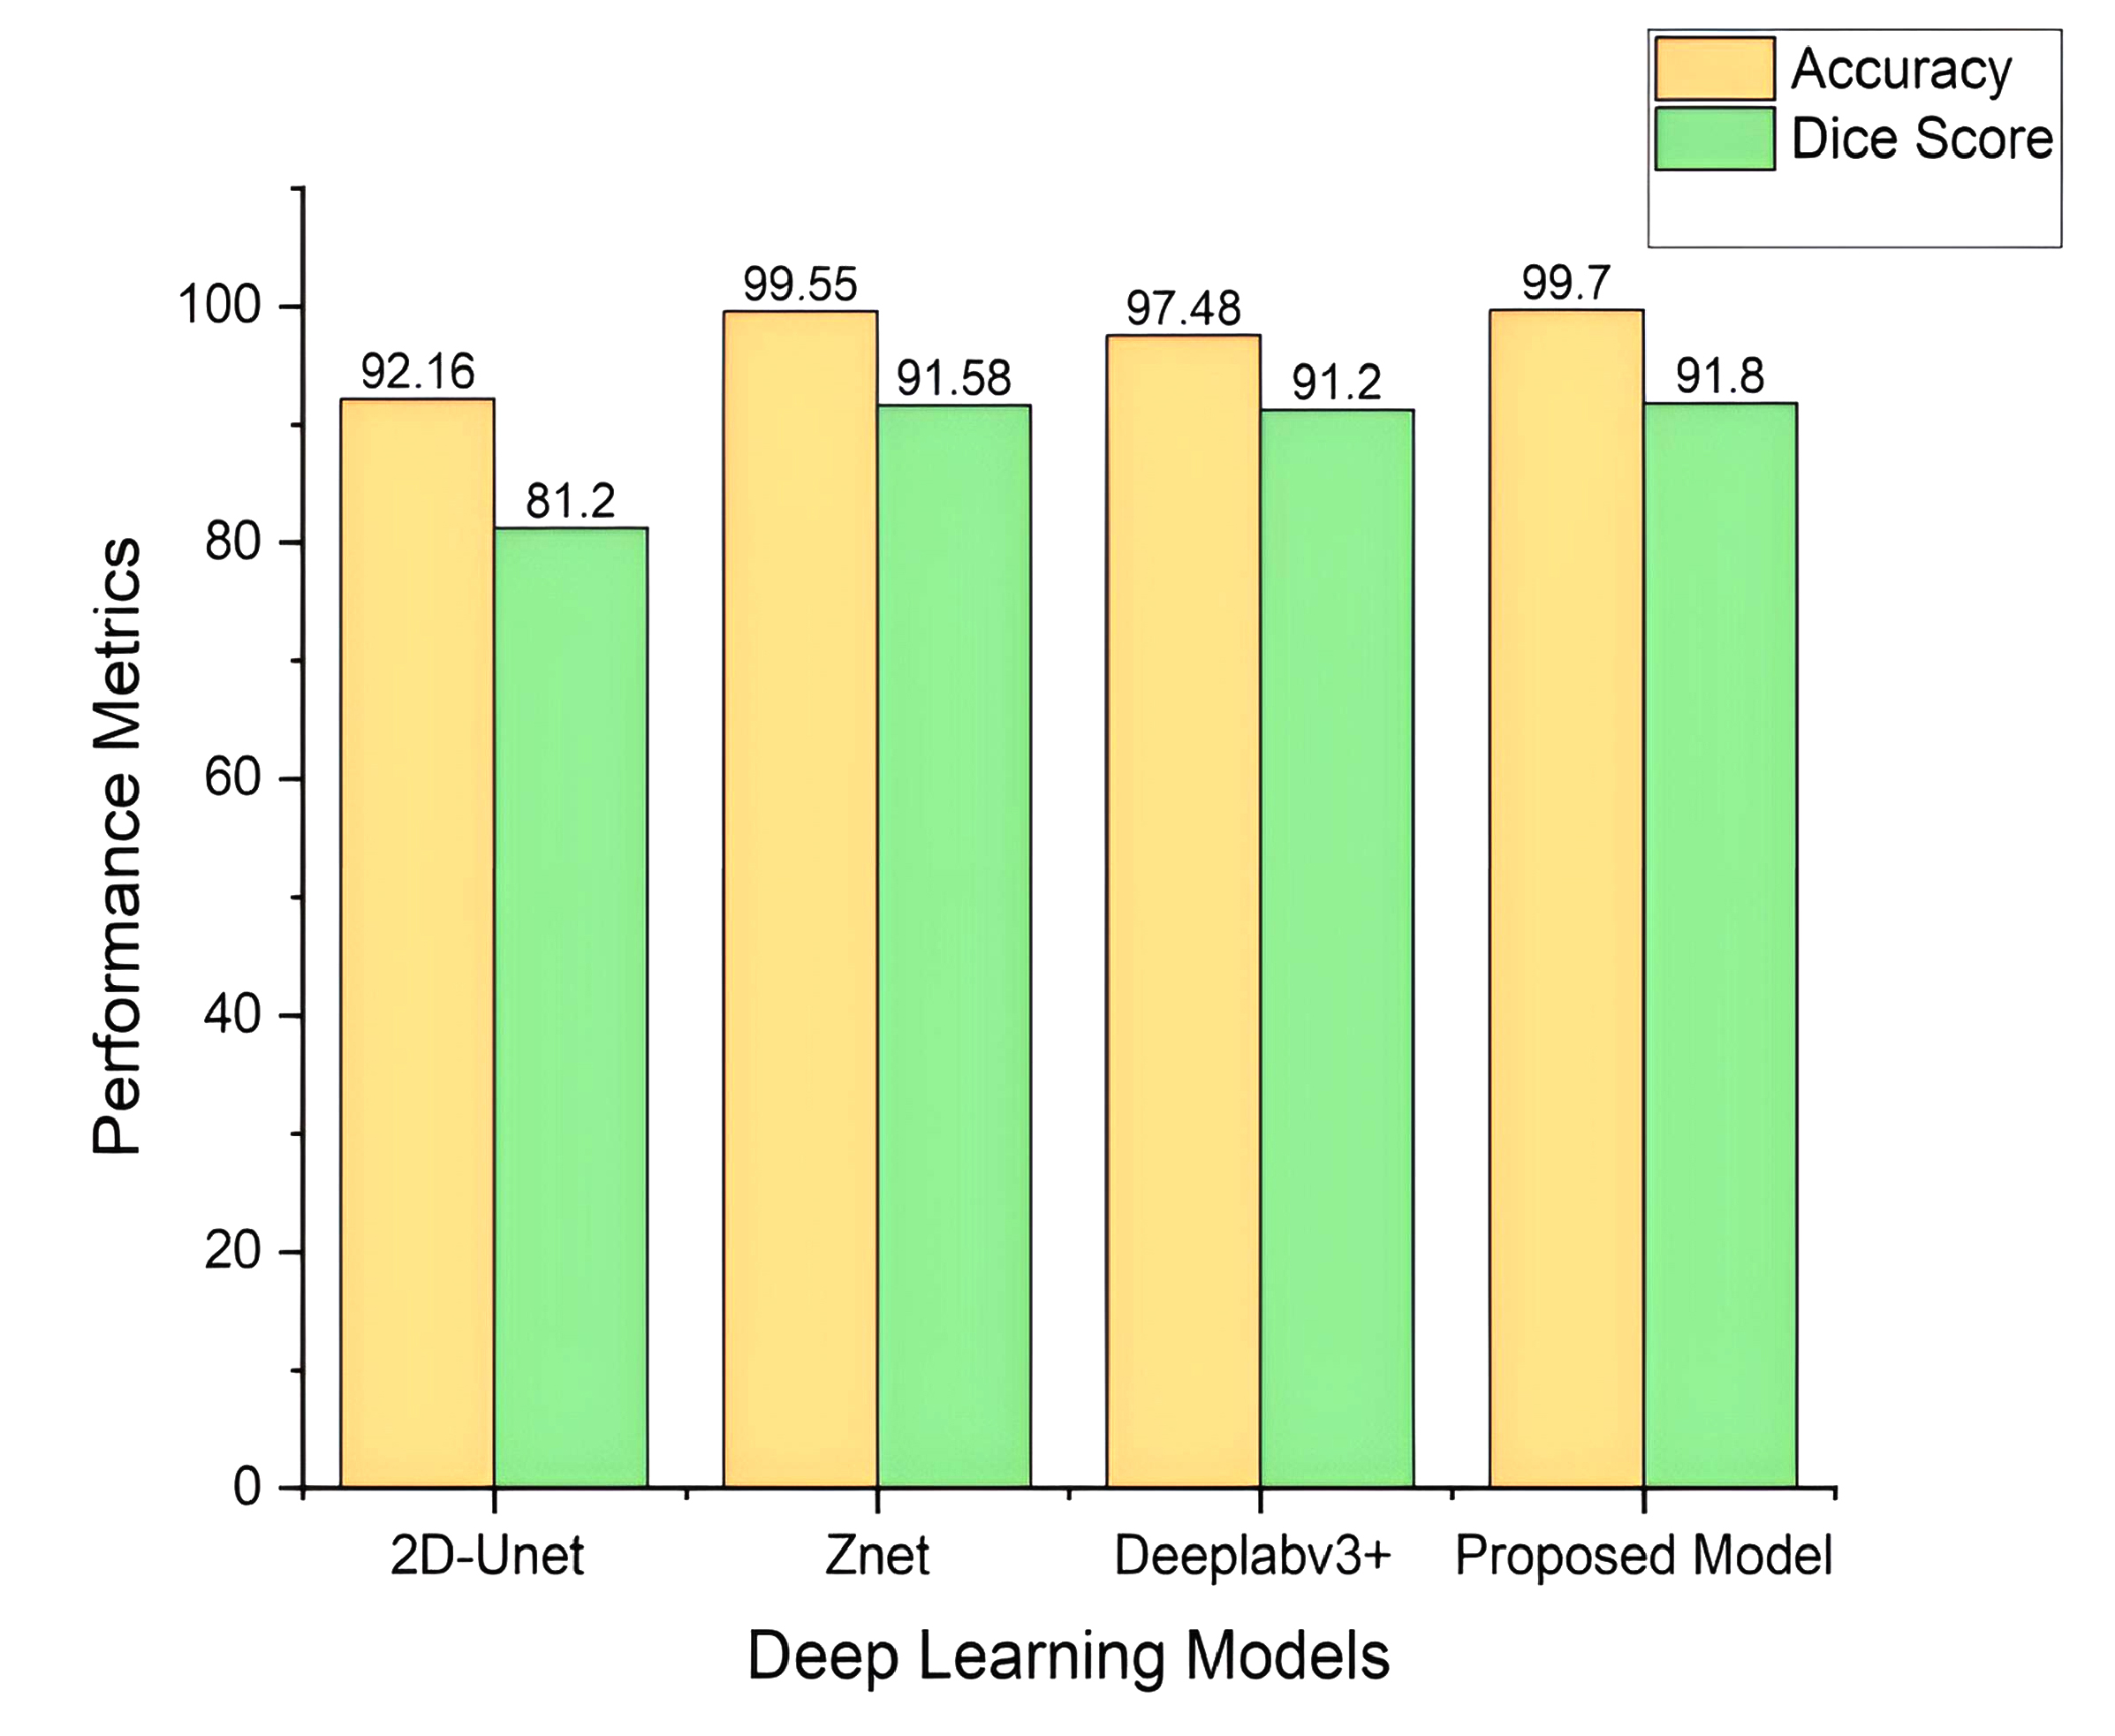

In this section, we conduct a comprehensive evaluation of the performance of our integrated YOLOv12-SAM 2 model in tumour segmentation. The model’s remarkable accuracy and capability in segmenting tumours are underscored by performance metrics, including a Dice coefficient of 91.8% and an accuracy of 99.7%. Our model outperforms alternative techniques, such as U-Net, DeepLabv3+, and other YOLO models, as indicated in Table 5. The Dice coefficient of 91.8% reflects a precise spatial overlap between the predicted masks and the ground-truth masks. Additionally, the 99.7% accuracy score highlights the model’s reliable ability to detect and segment tumours. YOLOv12 provides accurate localisation through bounding boxes, which are then used as prompts for SAM 2 to enable segmentation in regions with complex tumour boundaries. This combination of complementary detection (YOLOv12) and segmentation (SAM 2) mechanisms leads to more robust results, with fewer false positives and better generalisation across a wide range of MRI scans.

Although alternative methods, such as YOLONAS, YOLOv8 + U-Net, DeepLabv3+ + ResNet18, 2D-UNet, and Znet demonstrate commendable performance metrics, our proposed approach consistently surpasses them in terms of the Dice coefficient, highlighting its superior accuracy in tumour segmentation. The effectiveness of our method is particularly evident when compared to Znet, producing comparable outcomes in both accuracy and Dice coefficient. The high accuracy and Dice score demonstrate the model’s precision in segmenting and delineating tumour regions. These findings indicate that our model is a powerful tool in neuroradiology, capable of diagnosing brain tumours with greater precision, especially in complex cases that are challenging for human evaluation.

Figure (12) represents the comparative performance of YOLOv12+SAM2 and existing state-of-the-art models in terms of precision and Dice coefficient.

Comparative performance of YOLOv12+SAM2 and existing state-of-the-art models.